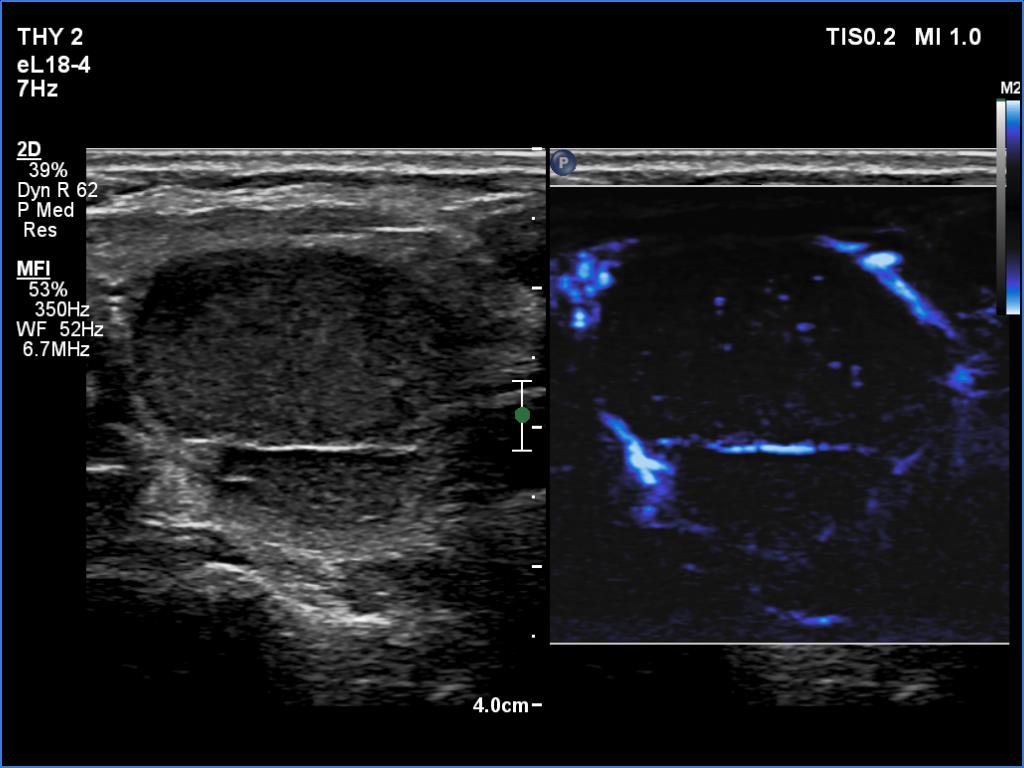

In the first part of the ultrasound examination, when the transducer was continuously moving over the thyroid gland, it was not detectable that the contents of the nodule were showing flow. When we stopped the transducer, it became clear that the seemingly solid mass was actually a dense liquid in a continuous flow. On Doppler examination, 'circulation' was visible in continuously changing places.

If it had really been about blood vessels, according to the cycle of circulation,

it would have disappeared once, at other times the flow would have reappeared, but at the same time we would have always seen it in the same place.

This case illustrates two rare phenomena. On the one hand, a dense liquid may appear to be a solid tissue. On the other hand, the Doppler assay actually detects fluid flow. In the vast majority of cases, of course, this displays a circulation in the blood vessels, but in the case of cysts, when pressure is applied to the fluid with the probe, a flow is created. In the case of flow in blood vessels, circulation is always seen in the same place, while in the case of flowing cystic fluid, the flow can be detected in constantly changing places.